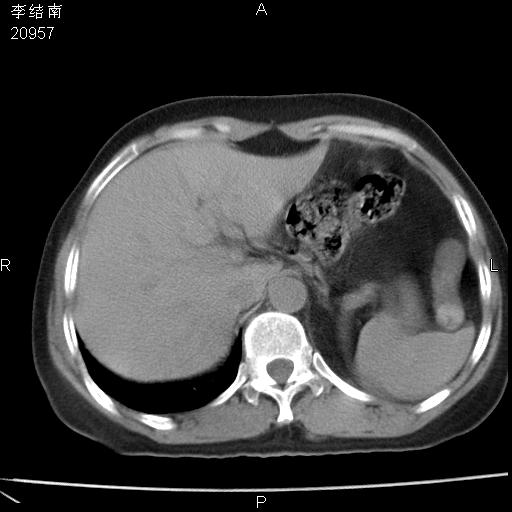

患者女,45岁,以右侧腰部包块来就诊,局部有压痛,皮肤颜色正常。因为是熟人扫的范围较大,患者有胆结石,胆源性胰腺炎病史。请大家看看,有手术病理。

可能大家觉得片子的质量不好,当时是做下腹部扫描,所以没有常规喝水,右腹壁的病灶当时是,密度不均有钙化影,局部骨质没见破坏,肝脏应该是受压的表现,所以当时考虑为腹壁的良性占位,各位老师考虑的神经源性肿瘤,我当时还真没想到,胰腺是胰腺炎治疗后改变.膈脚旁的混杂密度包快不好考虑什么,到上级医院做增强(腹部)+肺部平扫后,发现腹壁的病灶呈不均匀性强化局部可见囊性灶,当时考虑为腹壁结核,最具戏剧性的是膈脚旁的混杂密度灶确是胃的一部分,而腹壁的病灶确是脂肪瘤(简直不可思议)但是我亲眼所见在我们县医院开的.

很不好意思 ,患者后来手术切口裂开,临床医生作了病理证实是腹壁结核。

[病理诊断] CT13183腹壁结核!